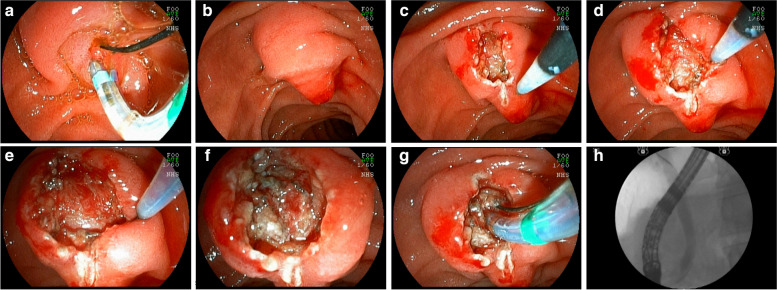

After identification and “palpation” with the tip of the fistulotome of the lateral limits of the papilla and exposure of the infundibulum, a wide, shallow incision only of the papillary mucosa was iniciated and, purely cut, with the fistulotome needle adjusted to approximately 2 mm, from top to bottom, just below the transverse crease, avoiding opening the region of the common channel. With the needle-knife, the needle was retracted, and the mucosal edges were pushed aside to expose the submucosa. Lateral incisions were made to expand the exposure and then superficial incisions were made to open the submucosa and, dissect thin layers one at a time, interspersed by blunt dissection with the tip of the needle-knife retracted; these steps were followed by identification of vessels, hemostasis and exposure of the sphincter muscle of the distal common bile duct. If bleeding occured, washing was performed with pressurized water through the fistulotome catheter itself or through the working channel of the duodenoscope, the bleeding point was identified and captured with hot biopsy forceps and sealed by seizure, rapid hemostasis was achieved by coagulation, and underlying thermal tissue damage was avoided. At this stage, transversal accessory incisions were made to remove the mucosa over the papilla and improve exposure (Fig. 2).

Subsequently, sectioning of the muscle fibers and of the common bile duct mucosa was performed, with bile outflow in most cases. Once the common bile duct mucosa was identified, the guide wire was introduced, confirmed by radioscopy and bile duct contrast (Fig. 3) (video 1).

However, in 63 cases (EFP failure), the guidewire was not passed into the common bile duct, most of the time due to minor bleeding or edema and loss of identification of structures in the dissection area. These cases were considered failure of the EFP in the first attempt. Of these 63 patients, 33 returned for a second attempt and what we found was a biliary fistula, with an easily identified orifice allowing the passage of the guide wire and the sphincterotome. However, in 30 cases, the patients did not return for the second attempt for various reasons. The reasons for non return were, worsening of the biliary obstruction or the clinical condition of the patient, complications of the underlying disease, the decision of the surgeon who conducted the case, and the indication of other alternatives for biliary drainage. As a result, 30 EFP patients did not return for the second attempt. Most of these cases were advanced cancer of the head of the pancreas that did not allow the guide wire to pass through the tumor. Such patients were referred for endoscopic ultrasound-guided biliary drainage, percutaneous transhepatic drainage or surgery.

This reinforces the idea that suprapapillary dissection is safer than countless unsuccessful attempts at cannulation through the ostium. The occurrence of acute post-ERCP pancreatitis is more dangerous than the sporadic occurrence of mild bleeding from papillary dissection, which is generally easily controlled. Another important point of the EFP procedure is that the wide exposure of the structures of the papilla leads to the formation of a fistula that, in most cases, is easily visualized by staining the bile around the fistular orifice, facilitating the cannulation of the bile duct (Fig. 6).